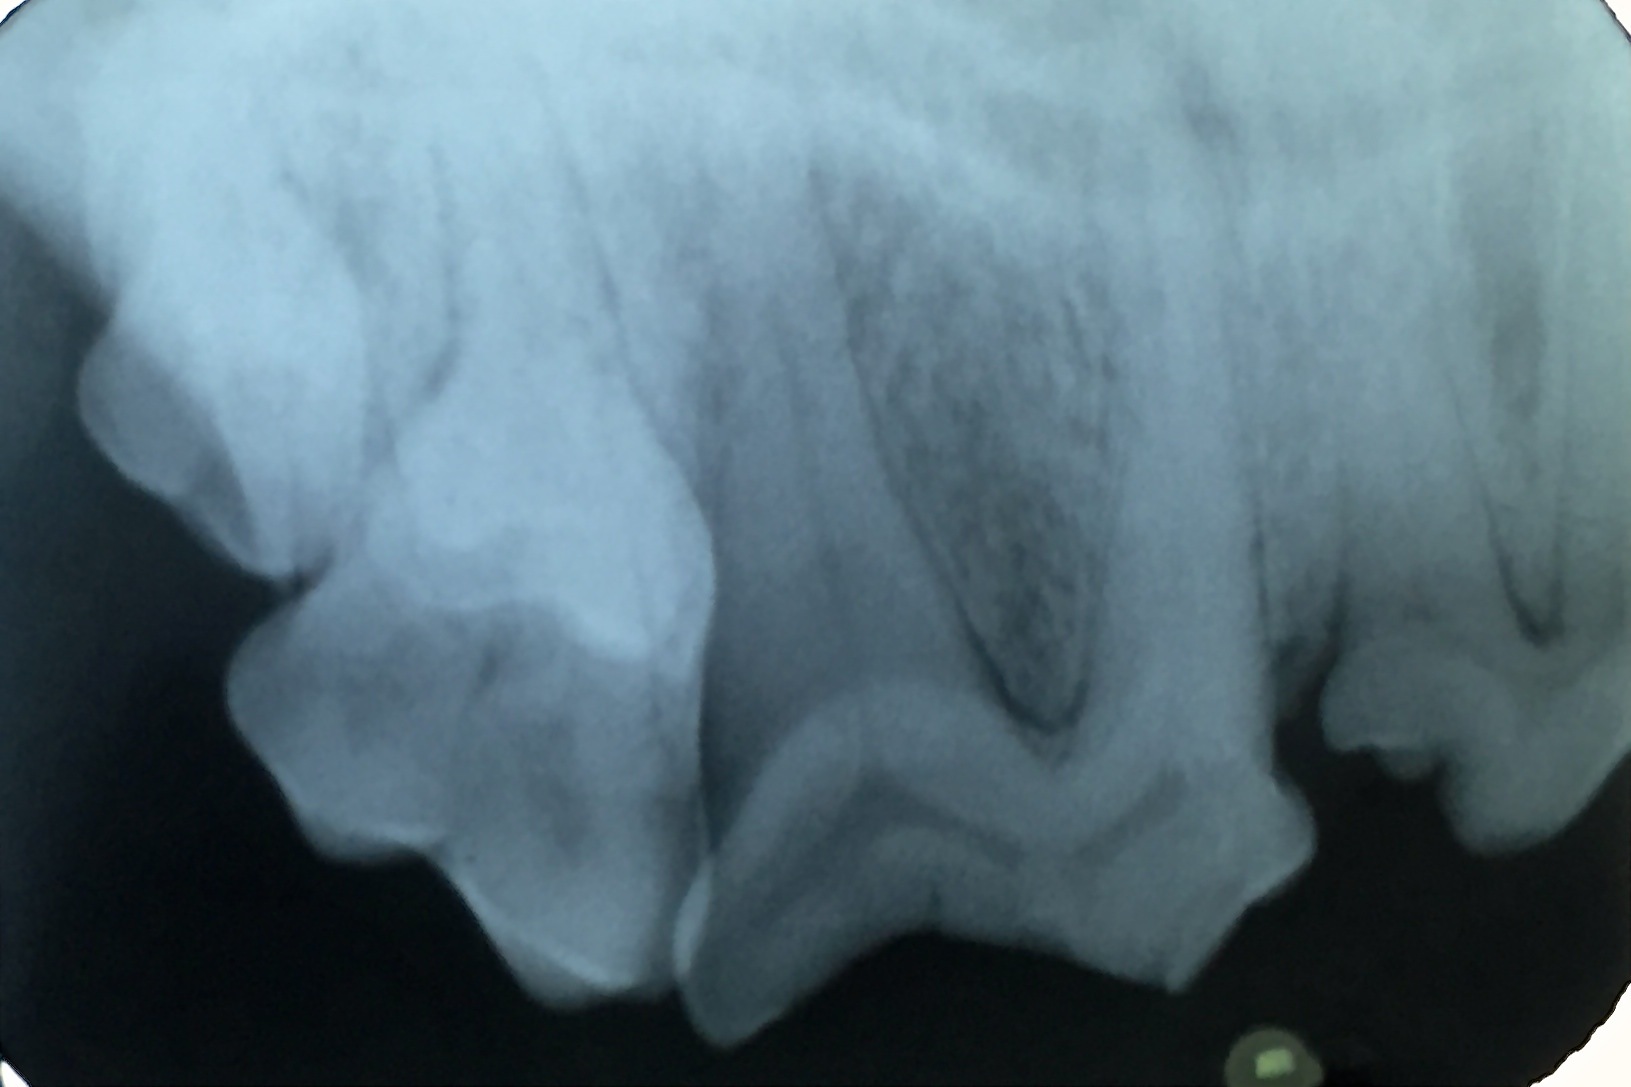

Vor der geplanten Operation brauchten wir jedoch noch einige Tropfen von Lottes Blut für eine Blutuntersuchung. Damit wollten wir weitere Erkrankungen ausschließen und das Narkoserisiko der bereits älteren Patientin (14 Jahre) minimieren. Im hauseigenen Labor haben wir die Leber- und Nierenwerte überprüft. Es lagen keine Veränderungen der Blutwerte vor, und so konnten wir mit der Operation noch am gleichen Tag beginnen. Nach Einleitung der Narkose fertigten wir zunächst ein Dentalröntgenbild des betroffenen Zahnes an, um das Ausmaß der Entzündung zu erkennen und weitere Frakturen in der Tiefe ausschließen zu können (Foto 4). Der Reißzahn ist der größte Backenzahn im Hundemaul und hat im Oberkiefer drei Wurzeln, darüber hinaus im Unterkiefer zwei. Funktionell sind diese beiden Zähne beim Zerkleinern des Futters am wichtigsten. Daher streben wir Tierzahnärzte immer an, sie zu erhalten und eine Wurzelkanalbehandlung mit anschließender Füllung durchzuführen.

Bei „Lotte“ lag jedoch eine komplizierte Fraktur mit gespaltener Krone vor, so dass tatsächlich nur eine Extraktion des Zahnes in Frage kam. Solch ein dreiwurzeliger Zahn kann nicht im Ganzen gezogen werden. Die Wurzeln sitzen fest im Kiefer und sind gerade bei schon älteren infizierten Zähnen sehr spröde und morsch und brechen leicht in der Tiefe ab. Daher ist eine kieferchirurgische, offene Extraktion die Methode der Wahl. So wurde bei „Lotte“ die Mundschleimhaut um den Zahn herum gelöst und der Kieferknochen freigelegt. Dann wurde der Knochen mit einem wassergekühlten Bohrer über den Zahnwurzeln entfernt, bis diese komplett sichtbar waren. Anschließend wurde der Zahn mit einem Fräser in drei Teile geteilt und die einzelnen Wurzeln mit verschiedenen Hebeln gelockert, um sie danach separat ziehen zu können (Foto 2). Besonders wichtig ist es, dass keine Wurzelreste im Kiefer verbleiben, denn diese verursachen weiterhin Schmerzen und führen zu einer Abszessbildung im Kieferknochen. Nach Glättung der scharfen Knochenkanten wurde die Schleimhaut wieder über die Wunde gelegt und mit einer Wundnaht mit Einzelheften eines resorbierbaren Nahtmaterials verschlossen, welches sich nach einigen Wochen von selbst auflöst (Foto 3).